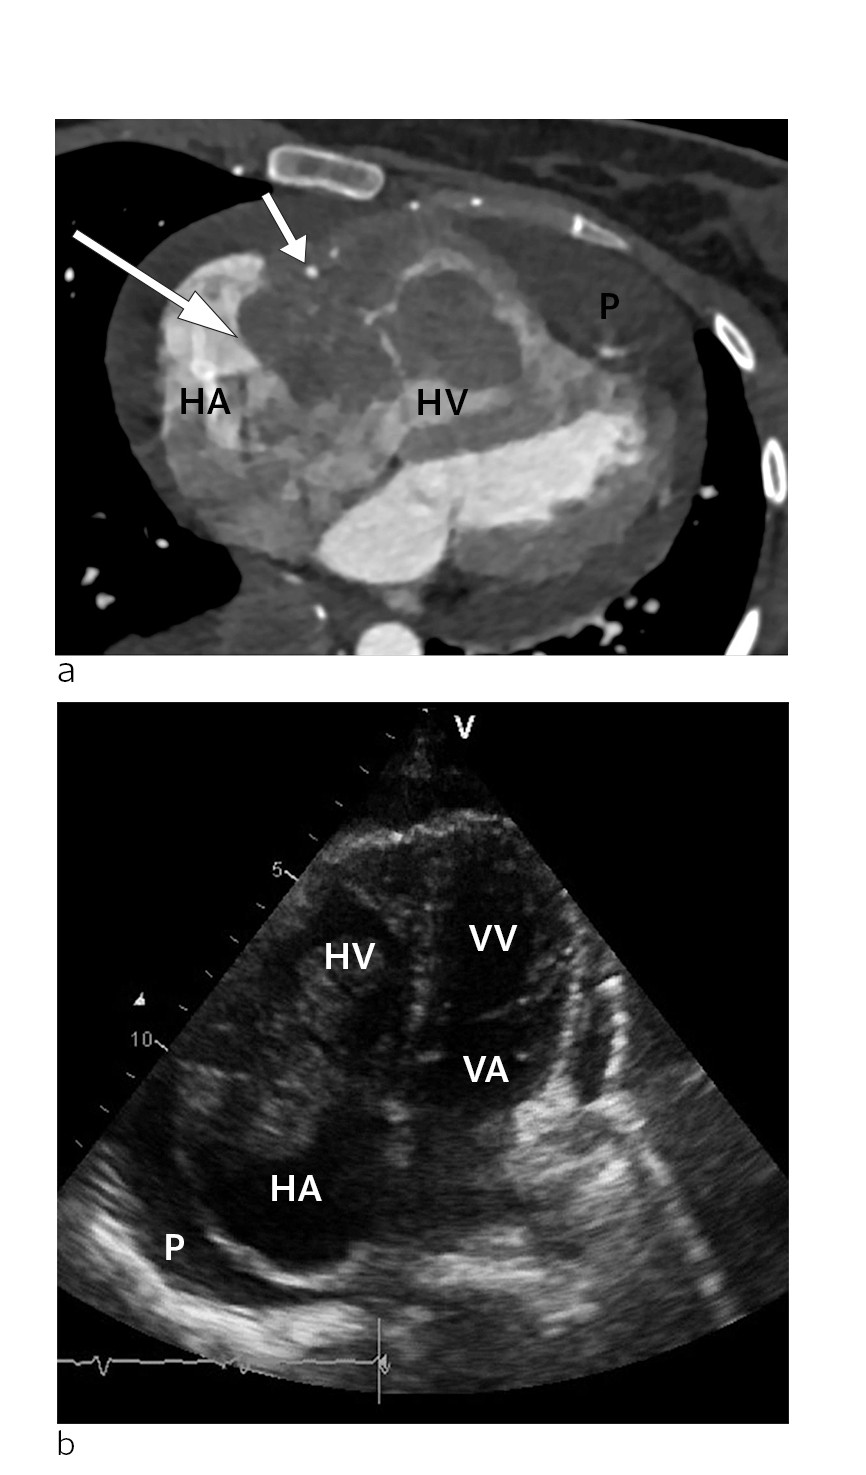

Etter funnet av bilyden vart det gjort ein orienterande ekkokardiografi i akuttmottaket. Denne viste to store oppfyllingar på høgre side i hjartet. Den største oppfyllinga målte 3,5 x 3 cm, var lokalisert i atriet og adherent til trikuspidalklaffeapparatet. I tillegg var det ei mindre oppfylling som òg penetrerte inn i høgre ventrikkel.

Det var tydeleg obstruksjon av den normale blodstraumen i trikuspidalostiet. I tillegg vart det påvist perikardvæske, mest uttalt langs høgre ventrikkel, med største brem målt til 1,5 cm, men utan at det var haldepunkt for tamponade. Det var normale forhold over mitral- og aortaklaff på venstre hjarteside. Funnet vart stadfesta med CT-undersøking av hjartet, som også gav mistanke om infiltrasjon av tumormassar i veggen til høgre ventrikkel med perikard (fig1).